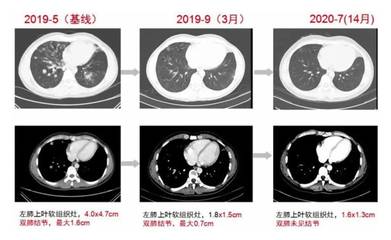

随着人们对健康的重视和低剂量螺旋CT的发展,越来越多的人检出肺结节。尽管如此,当很多人看到体检报告上“不能排除肺结节,北京四会西区医院中医肿瘤科钱艳芳主任说建议定期随访”的结论时,相信没有人不害怕,家住黑龙江的陈女士也不例外。陈女士今年55岁。2016年冬天,她因感冒咳痰。当地医院体检CT结果显示,肺结节呈斑片状,边界不清。医生建议随访。

2019年初,一个很冷的早晨,她感冒起床,咳嗽,痰中带血。在家人陪同下,到中国人民解放军总医院海南分院复查。CT结果显示左肺上叶纵隔及胸膜下见斑片,边界不清。双肺下叶增加一个直径约7mm的磨玻璃小结节,边界清晰。这次陈女士慌了,担心是肺癌。她想马上手术切除肺结节,但很多医生都拒绝了。医生说很可能是良性的,建议随访。